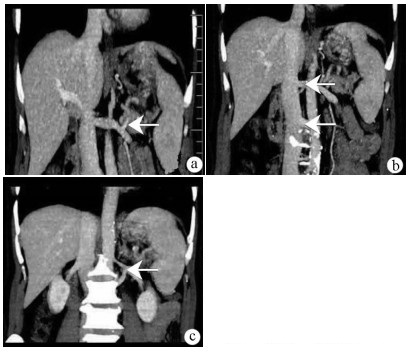

Research advances in hepatic echinococcosis with cavernous transformation of the portal vein

Maolin WANG, Yingmei SHAO

2021, 37(4): 965-968. DOI: 10.3969/j.issn.1001-5256.2021.04.053

Abstract(1023) HTML (406) PDF (1899KB)(33)

Abstract:

Compression by hepatic hydatid lesions may invade the portal vein and cause cavernous transformation of the portal vein (CTPV), which has difficulties and high risks in surgery, and conventional hepatectomy cannot achieve radical treatment. This article reviews the etiology, classification, clinical manifestations, and auxiliary examinations of hepatic echinococcosis with CTPV and summarizes the treatment strategies for this disease. It is believed that the treatment of hepatic echinococcosis with CTPV should combine the resection of hydatid lesions with the effective relief of portal hypertension, and revascularization and ex-vivo liver resection with auto-transplantation play an important role in radical resection.